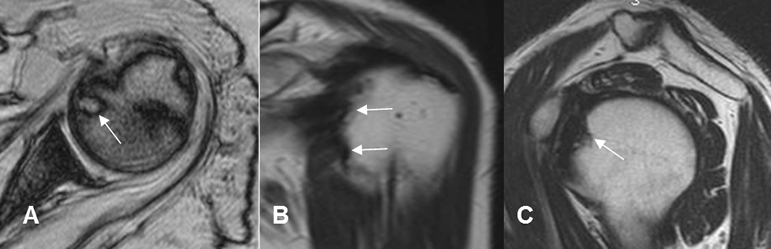

Fig 90. Pinzamiento interno anterior.

A: RM axial en FFE, B: RM coronal en T2 y C: RM sagital en T2. Pinzamiento interno, con erosión en la parte anteromedial del húmero.